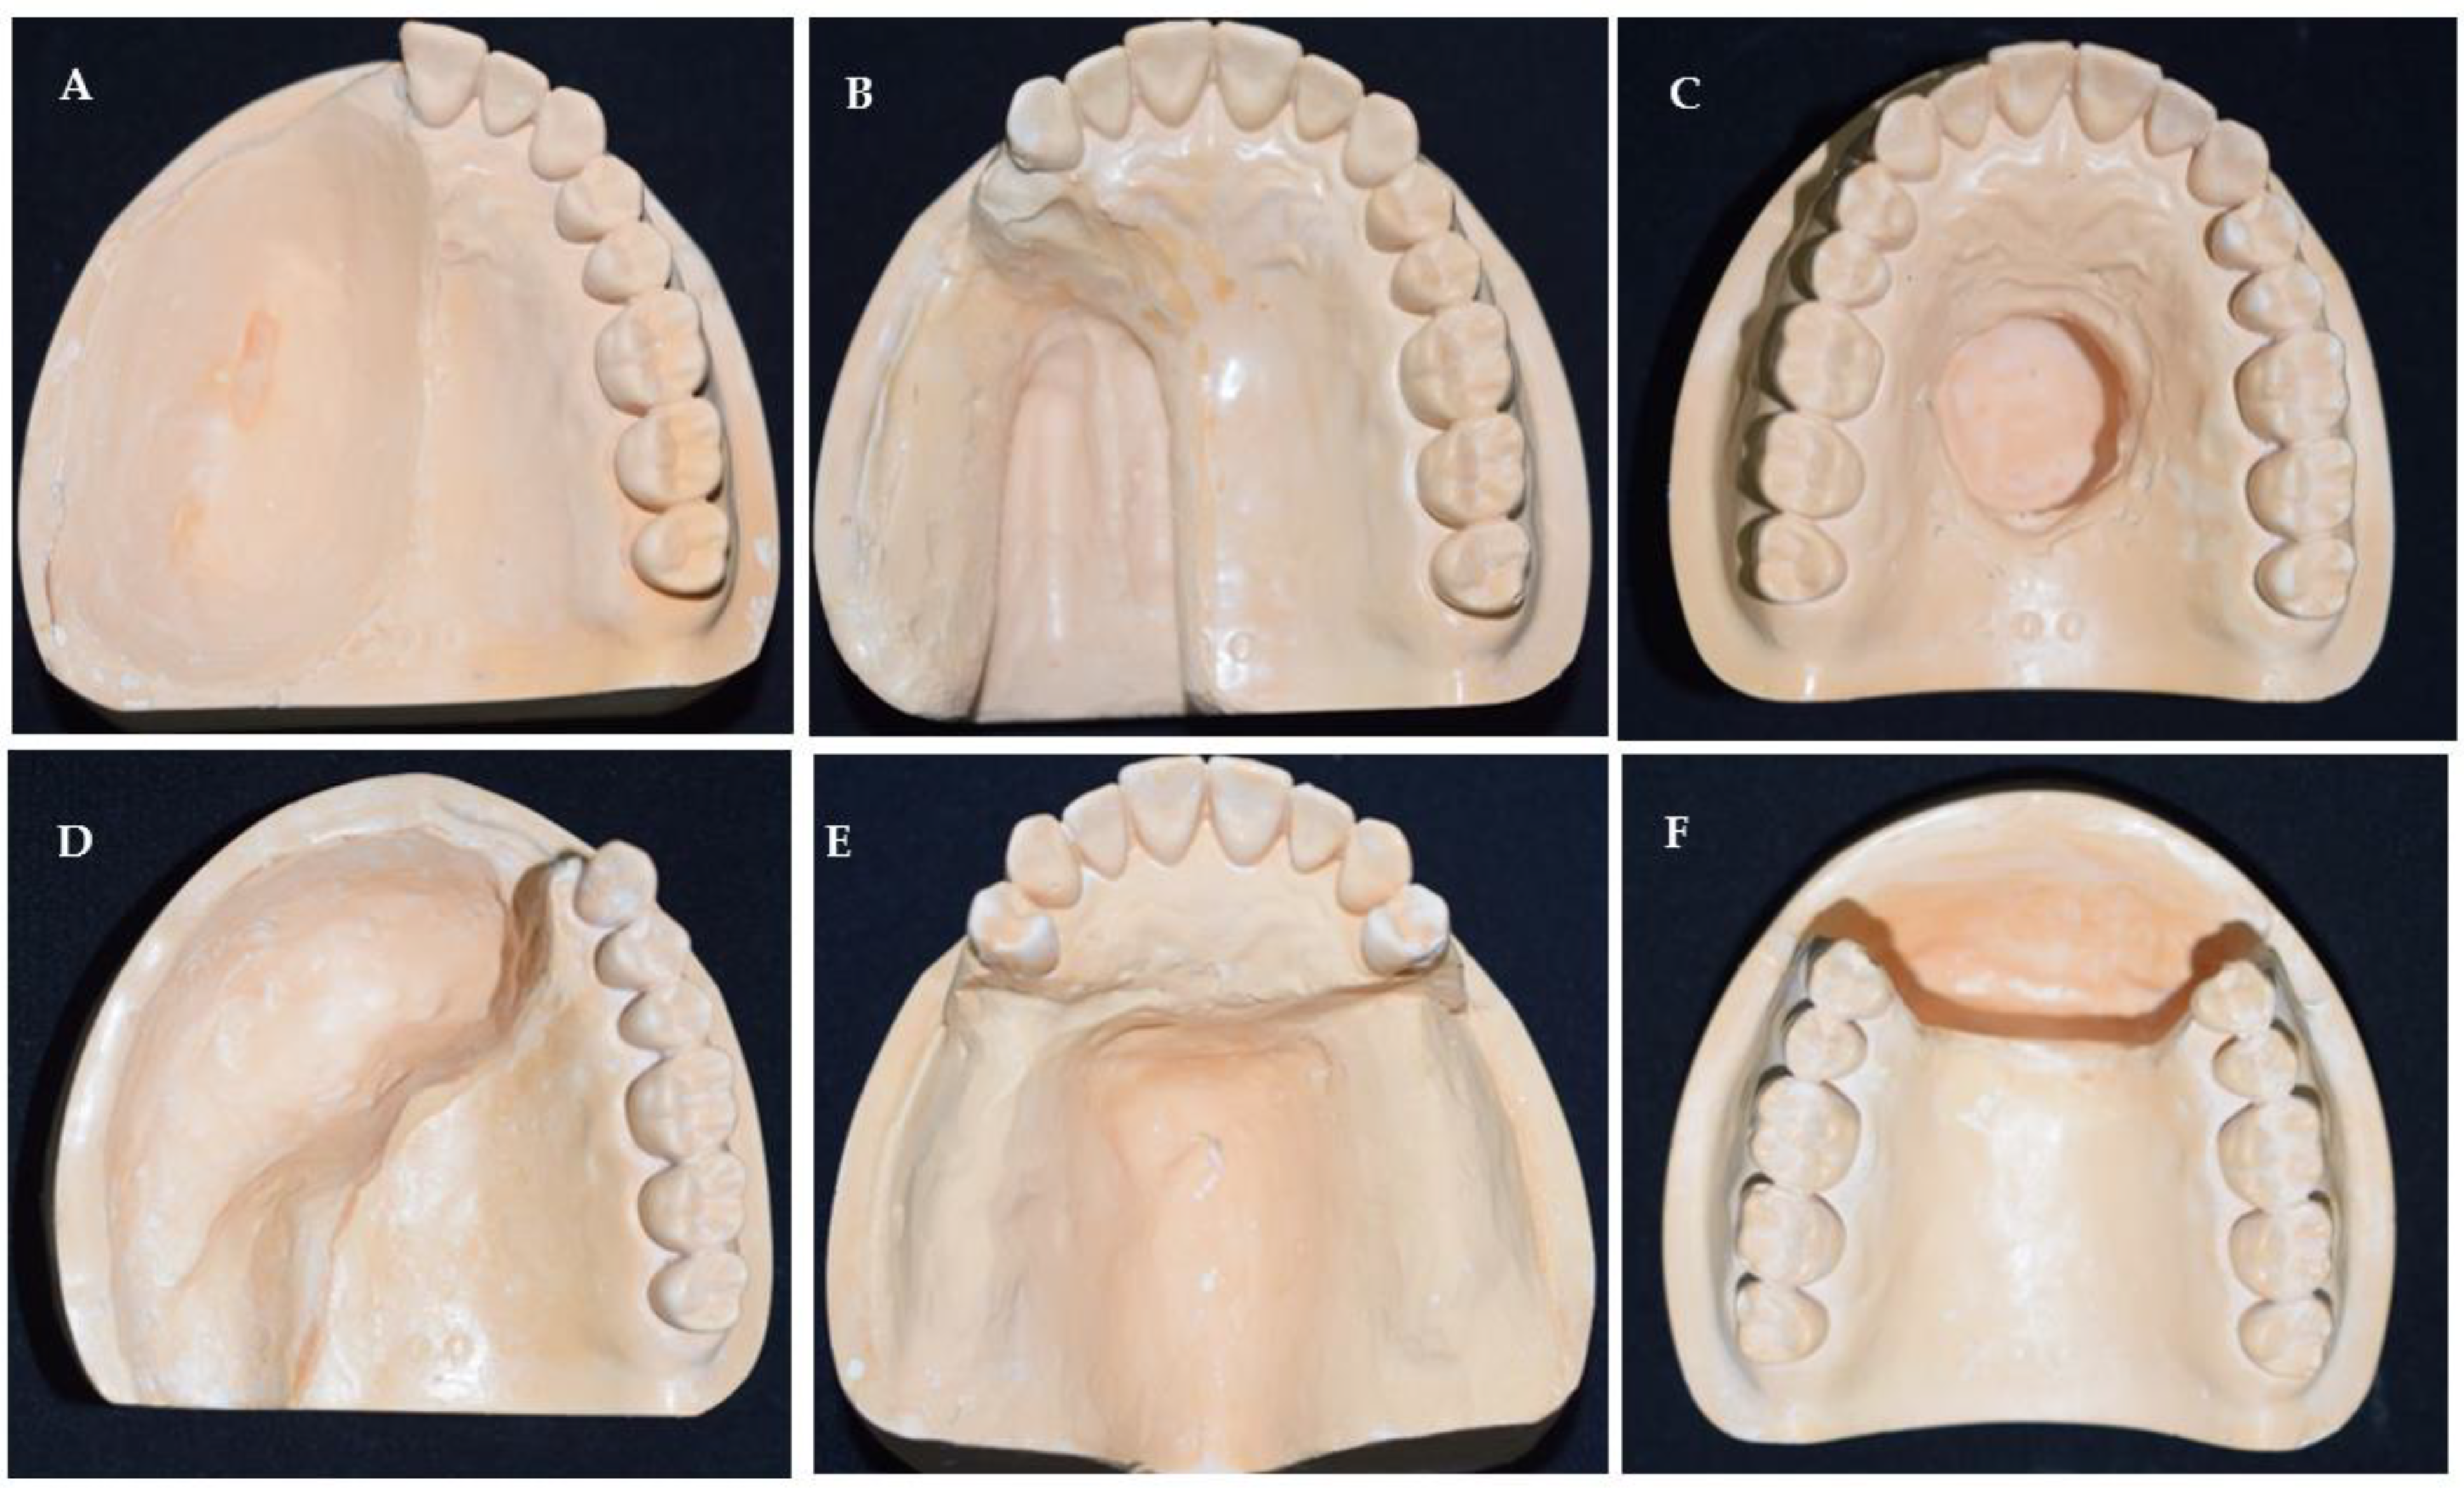

2.2. Sample Fabrication for Comparison Experiments

2.2.1. Conventional Impression Technique

2.2.2. Digital Technique